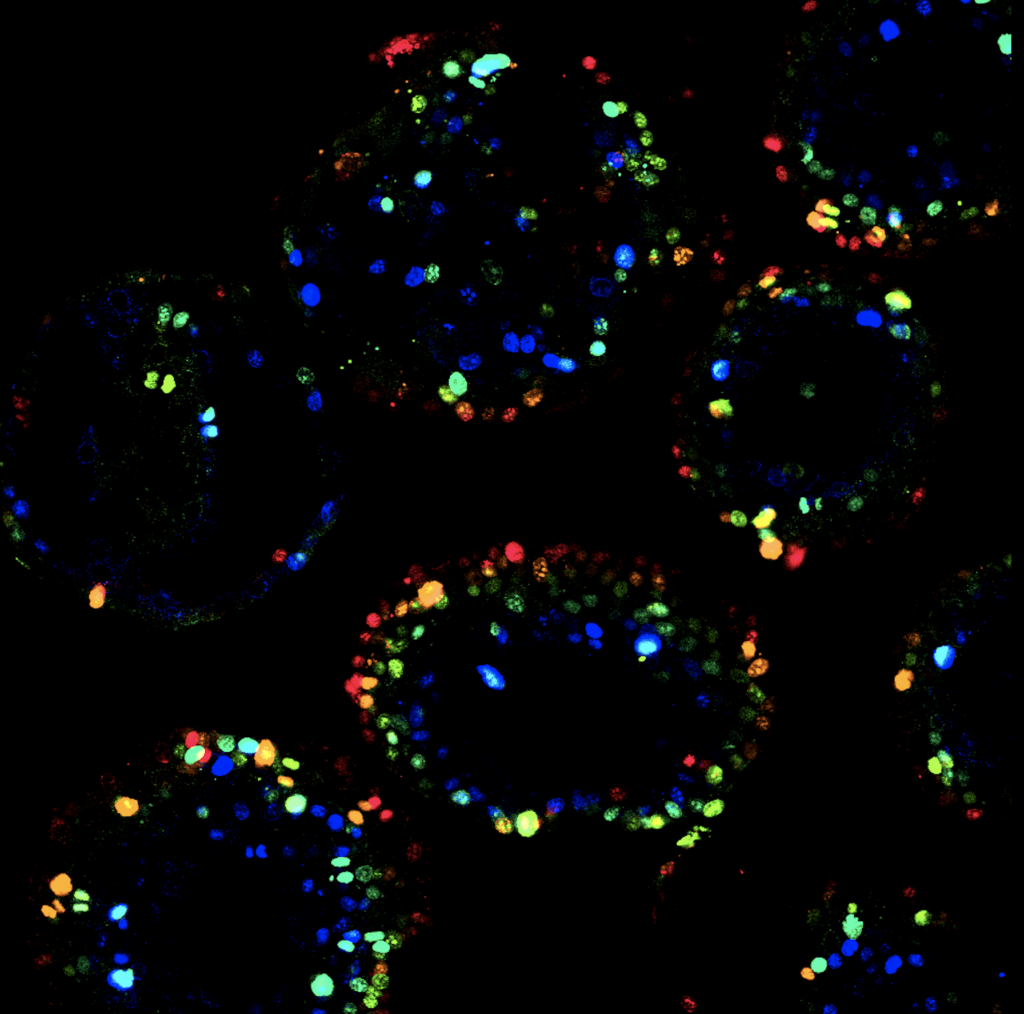

‘We used healthy human liver organoids in our research. Here, we developed a series of these mini organs, all with different DNA changes, mutations, that had previously been linked to FLC. We changed the genetic background of the organoids using the DNA modification technique CRISPR-Cas9, that works as a ‘molecular scissor’. Due to its rarity, there is not many tumor tissue available for research. Thanks to this technique we were able to study this tumor type now’ says Artegiani.

Hendriks and Artegiani constructed the liver organoid models by modifying the protein kinase A (PKA) complex using CRISPR-Cas9. PKA is a complex signaling protein, able to switch other proteins on or off. This ‘protein switch’ is made up of different units, each of them encoded by a different gene. Changes in the function of the different units through mutations seem to be crucial for the onset of FLC.

The organoids contained the so-called mutant fusion gene DNAJB1-PRKACA. This DNA change is very often found in FLC tumors. ‘When reconstructing this mutation in the organoids, we saw that it indeed is able to mirror multiple features of the tumors we see in patients with FLC. Yet, this single mutation caused a rather mild effect on the overall cellular and molecular behavior of the liver cells’ says Hendriks.

The situation completely changed when they introduced another set of DNA changes, also found in patients with FLC. ‘This second background not only contains a mutation in one of the PKA genes, PRKAR2A, but also in an additional gene called BAP1. In this case, the organoids presented features typical of an aggressive cancer. This suggests that different genetic FLC backgrounds lead to different degrees of tumor aggressiveness’ says Artegiani. Next to this, the greatly enhanced transforming effect caused by the BAP1 and PRKAR2A mutations allows the cells to adapt to different environments. This possibly explains the uncontrolled growth of cells during FLC tumor formation.

However, during the study, this turned out to be particularly difficult for FLC. ‘The main cause is that these tumors present features of both hepatocytes and ductal cells, the two most important cells in the liver. Our organoids showed that the cooperation of PRKAR2A and BAP1 transformed an originally healthy hepatocyte into a ductal cell, with increased cancer stem cell features. This transformation of a cell type into another one is called transdifferentiation. This is a particularly interesting phenomenon that could happen in various tumors, and makes the identification of the cell-of-origin very difficult. However, with the use of our models, we were able to uncover the hepatocytes as the probable cell-of-origin’ says Artegiani.